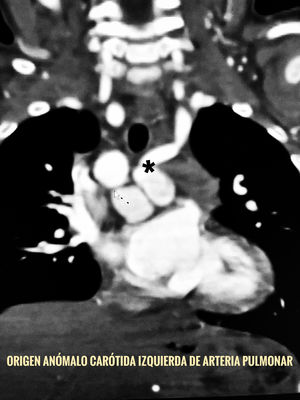

Caso clínicoPaciente femenina de un año de edad, con antecedentes de síndrome de Holt Oram, reflujos gastroesofágico y vesicoureteral; en seguimiento cardiológico desde los dos meses de edad por Comunicación Interauricular (CIA) e Interventricular (CIV) además de estenosis pulmonar valvular con saturación arterial alrededor de 85%. En el ecocardiograma se comprobaron los defectos mencionados, además de estenosis infundibular ligera y valvular pulmonar severa. Se apreció imagen anómala en el arco aórtico que no se definió adecuadamente por lo que se realizó una AngioTAC que confirmó las comunicaciones interauricular y ventricular, y evidenció el origen anómalo de la arteria carótida común interna desde el tronco de la arteria pulmonar (figs. 1 y 2). No se describen síntomas ni signos dependientes del vaso anómalo, a saber robo de la carótida ni hiperflujo pulmonar en la historia clínica previa. De igual forma se evaluó la integridad del polígono de Willis. En el miembro superior derecho se comprobó radiológicamente la ausencia del radio y tres falanges en el pulgar, como una variante del síndrome de Corazón Mano.

Para el diagnóstico de la ACCIA, es importante una reconstrucción tridimensional mediante la AngioTAC que ayuda al reconocimiento de patrones anatómicos inusuales como el origen anómalo vascular. La resonancia magnética de igual forma permite evaluar detalladamente el suministro arterial aberrante2,9.